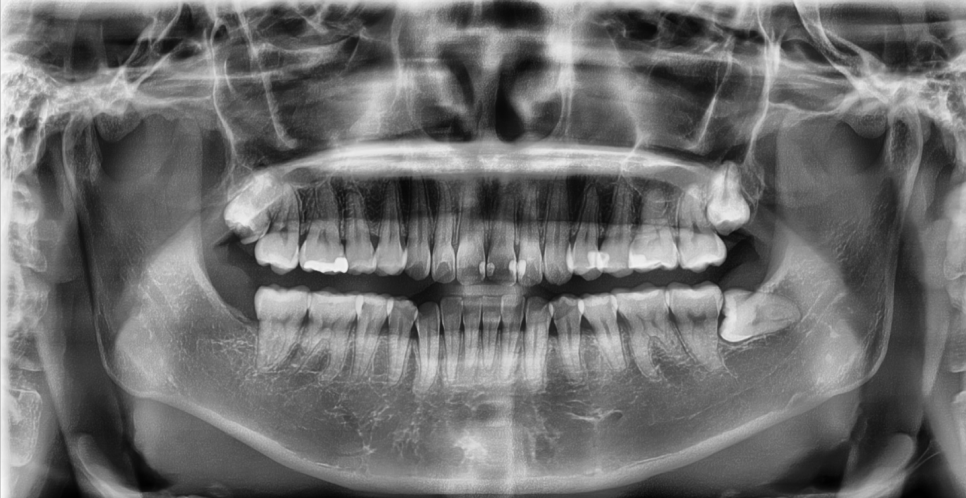

삭제를 최소화 할 수 있는지 확인

파노라마 X-ray, 구강스캐너, 교합 체크까지

전체적으로 살펴본 결과입니다

앞니 치질이 충분히 남아 있었고

잇몸 라인도 건강하게 유지되어 있었습니다.

이런 경우에는 삭제를 거의 하지 않거나

무삭제로 진행하여 자연치를 최대한

살리면서 시술할 수 있습니다.

무엇보다 라미네이트를 위해

많이 깎아야 하는 치아가 단 한 개도 없었기 때문에

‘무삭제 라미네이트’가 가능한 최적의 케이스였어요.